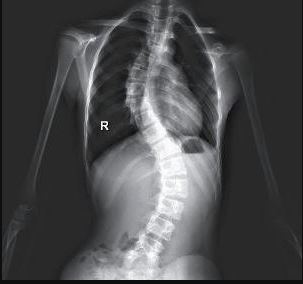

特发性脊柱侧凸(AIS)是一种进展性疾病,但进展原因始终是个“迷”,成为临床治疗的难点一直困扰着医生。如果能建立对AIS患者疾病进展的精准预测模型,进行早期干预,就可以让部分AIS患者免遭手术的痛苦。

特发性脊柱侧凸作为一种严重影响青少年身心健康的常见脊柱畸形已引起高度关注。由于疾病进展机制尚不明确,不同个体进展程度也大不相同。

有一部分患者侧凸进展较慢,通过定期观察,形体训练及支具控制,病情得以逆转,保留正常人一样的脊柱功能,并终生无需再治疗。但是也有一部分患者,侧凸进展迅速,可能压迫内脏器官,造成器官功能衰竭,这类患者只能手术治疗,这不仅造成患者身心创伤,而且增加了治疗的风险及费用,更重要的是术中固定节段的脊柱在术后将永久失去活动功能。因此,如何预测AIS的进展情况一直是脊柱外科医生的难题。